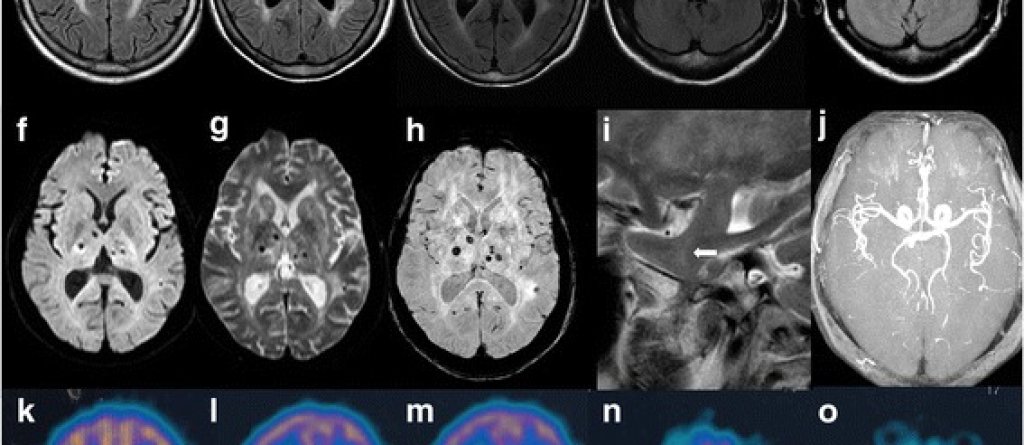

Снимка: Tingting Lu, Yuhang Pan, Lisheng Peng, Feng Qin, Xiaobo Sun, Zhengqi Lu, and Wei Qiu [CC BY 4.0 (https://creativecommons.org/licenses/by/4.0)]